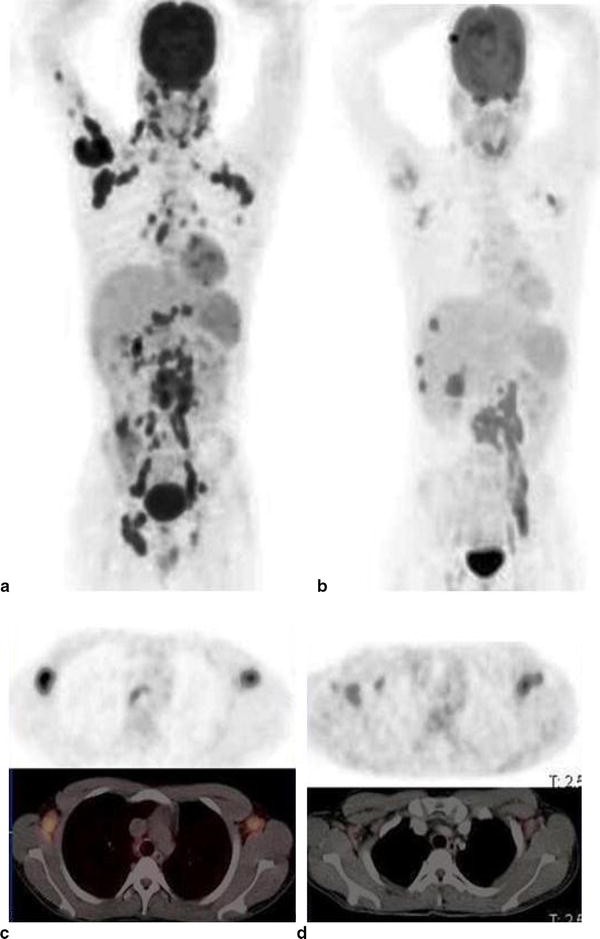

Pet Ct Scan For Infection . Combining a pet scan with an mri or ct scan can help make the images easier to interpret. Positron emission tomography, also called pet imaging or a pet scan, is a diagnostic examination that involves getting images of the. At left is a ct scan, while the center image is a pet scan. A positron emission tomography (pet) scan detects abnormal cell metabolism to diagnose cancer, heart disease, and brain disorders. The image on the right is. [ 18 f] has good. Pet scans play can play an important role in the detection of infections, offering a view of the body’s metabolic activity. For example, combining a pet scan with a ct scan (pet/ct) can provide more comprehensive information. A number of practical advantages make fdg pet/ct one of the procedures of choice for assessment of patients with infection and inflammation. Learn about the benefits of a pet scan and.

For example, combining a pet scan with a ct scan (pet/ct) can provide more comprehensive information. Learn about the benefits of a pet scan and. At left is a ct scan, while the center image is a pet scan. [ 18 f] has good. Positron emission tomography, also called pet imaging or a pet scan, is a diagnostic examination that involves getting images of the. The image on the right is. Combining a pet scan with an mri or ct scan can help make the images easier to interpret. Pet scans play can play an important role in the detection of infections, offering a view of the body’s metabolic activity. A positron emission tomography (pet) scan detects abnormal cell metabolism to diagnose cancer, heart disease, and brain disorders. A number of practical advantages make fdg pet/ct one of the procedures of choice for assessment of patients with infection and inflammation.

The role of PETCT in imaging infection. (A) Transaxial and (B) coronal Pet Ct Scan For Infection The image on the right is. At left is a ct scan, while the center image is a pet scan. [ 18 f] has good. Pet scans play can play an important role in the detection of infections, offering a view of the body’s metabolic activity. For example, combining a pet scan with a ct scan (pet/ct) can provide more. Pet Ct Scan For Infection.